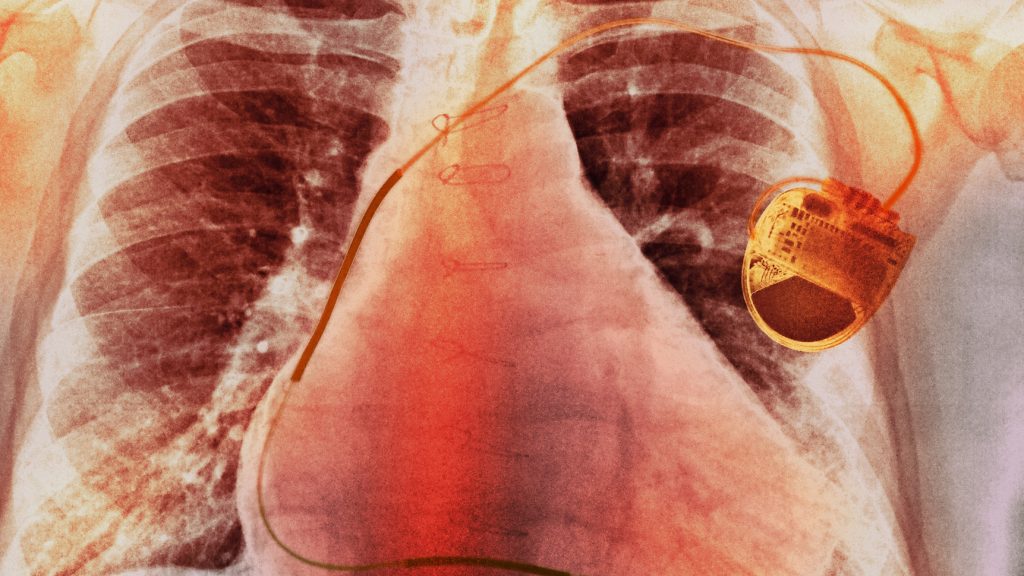

Megalkották a pacemakert, amit aksi helyett a szív lát el en...